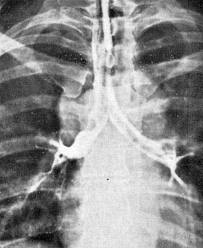

ДИАГНОСТИКА

Диагноз устанавливается на основании анамнеза, клинических проявлений, данных обзорной рентгенографии, томографии, трахеобронхоскопии, спирографии, бронхографии, а также лабораторных исследований крови.

Медицинские процедуры, проводимые при заболевании бронхостеноз: Бронхоскопия, Бронхография, Рентгенография грудной клетки, Компьютерная томография, Спирография при записи на автоматических аппаратах, Клинический анализ крови, Исследование газов крови